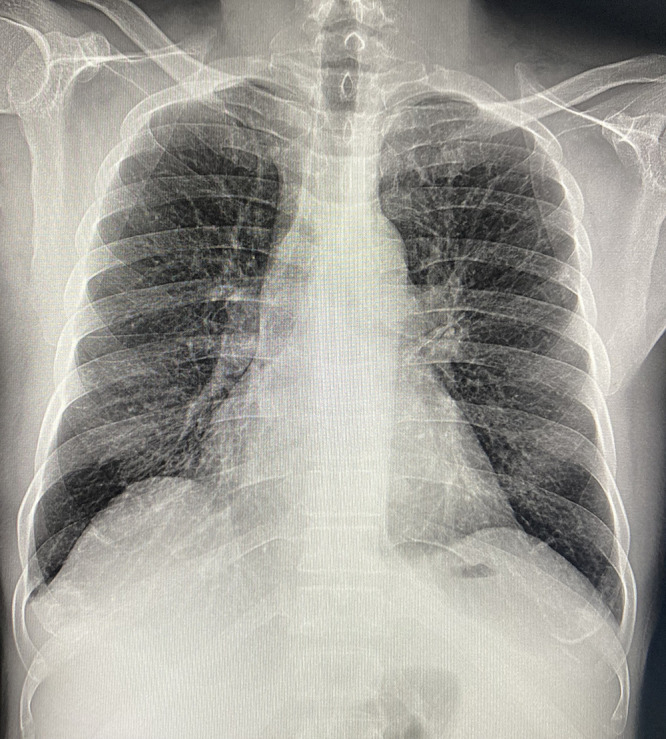

We present the case of an HIV-positive man diagnosed with multicentric Castleman disease (MCD) associated with human herpesvirus 8 (HHV8) infection, complicated by renal failure. This subtype of an otherwise rare disease is a complication of HIV and HHV8 infection. The diagnosis and management of HHV8-MCD in the developing world is challenging-in part due to its rarity, but largely due to the limited access to histology and other laboratory services. Our case presented with a confusing constellation of symptoms and was diagnosed with MCD on histology. Here we discuss the epidemiology, pathogenesis, diagnosis, and treatment of HHV8-MCD in the context of HIV infection in a resource-limited setting, in the hope that greater awareness will lead to more prompt recognition.